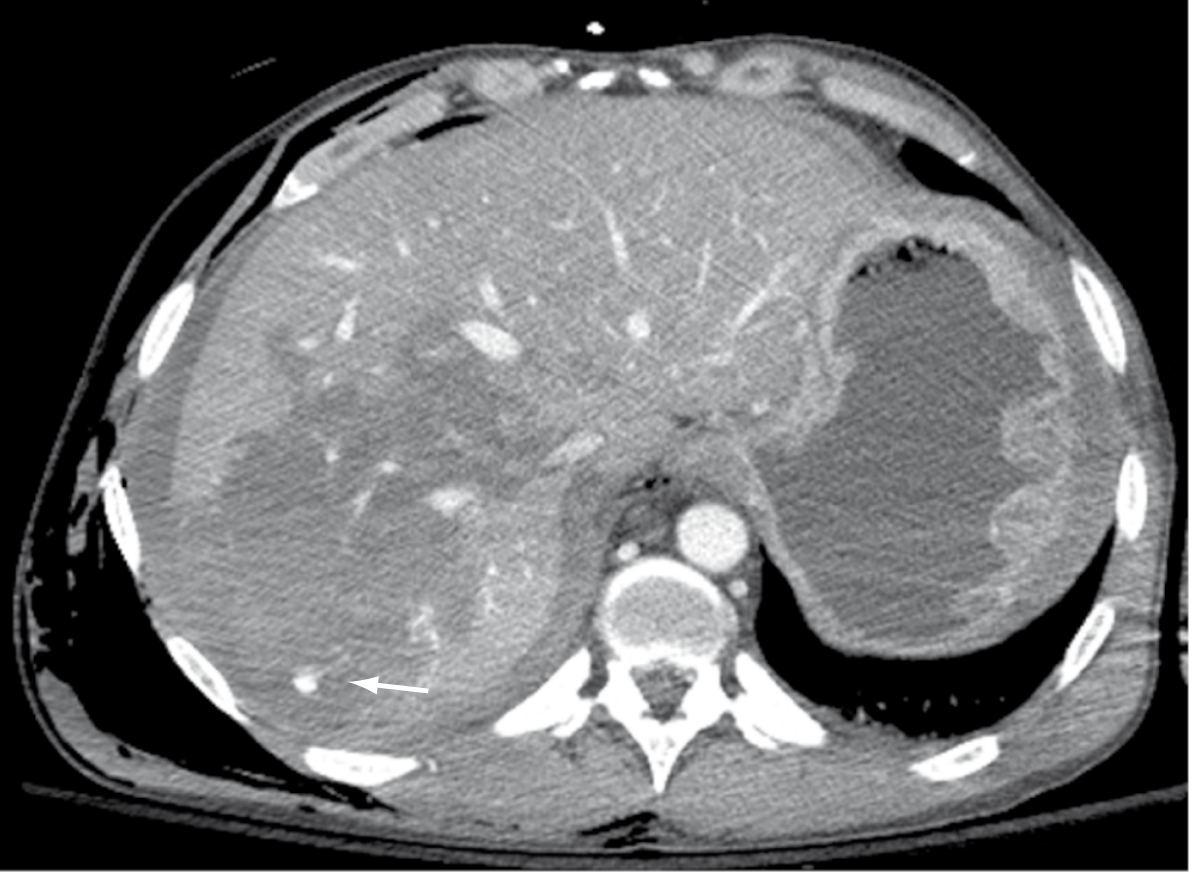

CT images of liver injury:

CT of liver injury grades

CT liver injury

CT images of liver injury — Current Surgical Therapy 14e, p. 1342

Grade IV liver laceration (Sabiston)

Grade IV liver laceration with active extravasation (arrow) — Sabiston Textbook of Surgery, p. 692